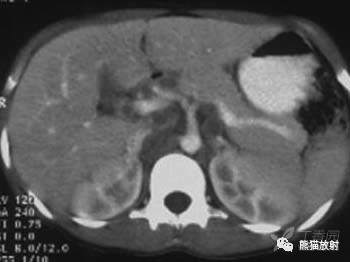

肝门区及腹膜后多发肿大淋巴结,部分融合,密度较低,环形强化。